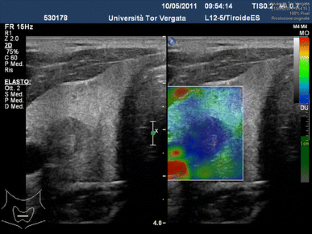

The aim of this study was to determine the accuracy of elastosonography in the differential diagnosis of thyroid nodules using a qualitative [evaluation of the stiffness score (SS)] and quantitative assessment [evaluation of the strain ratio (SR)].

Forty-four nodules were malignant (TIR ≥ 3) and 324 benign on cytological analysis. Considering a cut-off of SS > 2, we had 91 % sensitivity, 68 % specificity, 27 % PPV and 98 % NPV. Considering a cut-off of SR ≥ 3.28, we had 81.8 % sensitivity, 82.7 % specificity, 39.1 % PPV and 97.1 % NPV.

The SR calculation did not provide additional data to the SS, which remains the elastosonography benchmark. It will be necessary to validate these preliminary data by larger prospective randomised trials.